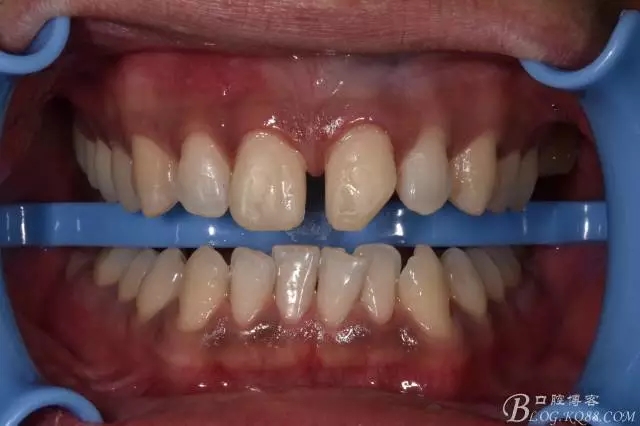

術(shù)后即刻照

口內(nèi)照